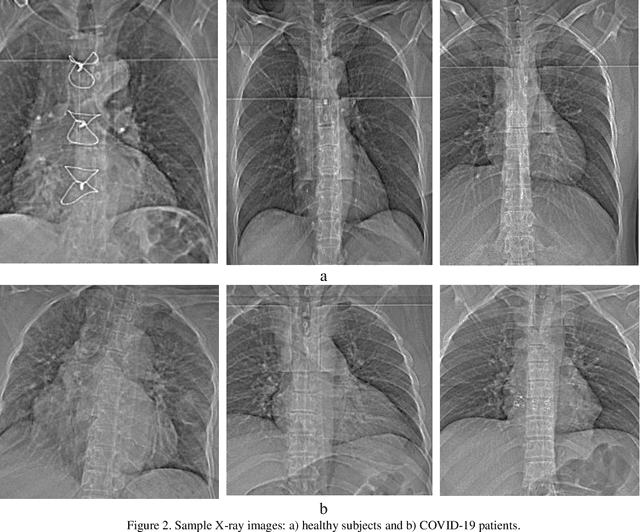

Abstract:The coronavirus (COVID-19) is currently the most common contagious disease which is prevalent all over the world. The main challenge of this disease is the primary diagnosis to prevent secondary infections and its spread from one person to another. Therefore, it is essential to use an automatic diagnosis system along with clinical procedures for the rapid diagnosis of COVID-19 to prevent its spread. Artificial intelligence techniques using computed tomography (CT) images of the lungs and chest radiography have the potential to obtain high diagnostic performance for Covid-19 diagnosis. In this study, a fusion of convolutional neural network (CNN), support vector machine (SVM), and Sobel filter is proposed to detect COVID-19 using X-ray images. A new X-ray image dataset was collected and subjected to high pass filter using a Sobel filter to obtain the edges of the images. Then these images are fed to CNN deep learning model followed by SVM classifier with ten-fold cross validation strategy. This method is designed so that it can learn with not many data. Our results show that the proposed CNN-SVM with Sobel filtering (CNN-SVM+Sobel) achieved the highest classification accuracy of 99.02% in accurate detection of COVID-19. It showed that using Sobel filter can improve the performance of CNN. Unlike most of the other researches, this method does not use a pre-trained network. We have also validated our developed model using six public databases and obtained the highest performance. Hence, our developed model is ready for clinical application